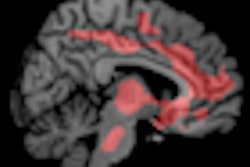

Senior author Bradley Schlaggar, MD, PhD, a pediatric neurologist and associate professor of neurology, and colleagues used a resting-state functional connectivity MRI scan. By correlating increases and decreases in blood flow to the various brain regions as subjects rest in the scanner, it can be determined which of these regions work together in brain networks.

In a recent study, Washington University scientists showed that as the brain matures, brain networks change. The brain's overall organization switches from networks involving regions physically close to each other, which is the dominant motif in a child's brain, to networks that connect distant regions, the primary organizational principal in adult brains.

Dosenbach used data from five-minute MRI scans of 238 psychologically normal individuals ranging in age from 7 to 30 years. The support vector machine analyzed approximately 13,000 functional brain connections and selected the best 200 to produce a single index of the maturity of each subject. The data allowed the researchers to predict whether subjects were children or adults, and roughly formed a curving line that tracks the path of normal functional brain development.